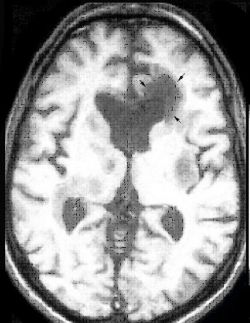

Нейроинфекцией называют заболевания головного, спинного мозга или нервных проводников, которые были вызваны попаданием в организм микроба, вируса или грибов. Лечение таких инфекций должно быть начато своевременно и адекватно, так как в некоторых случаях счет может идти на часы.